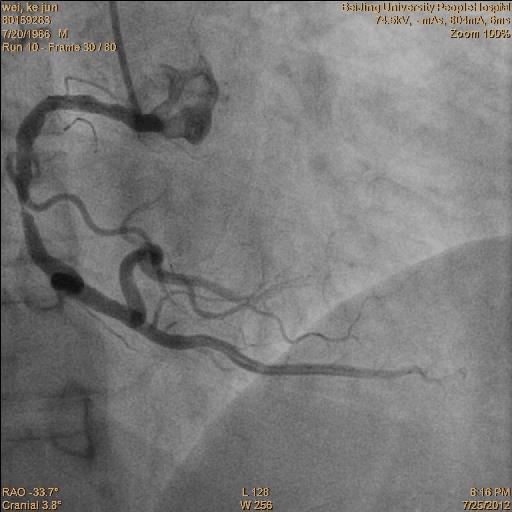

冠脉造影提示:双支病变。 见下图:

•术后一周复查造影,了解LIMA桥的状况,同时行RCA 和D的介入治疗。见下图: